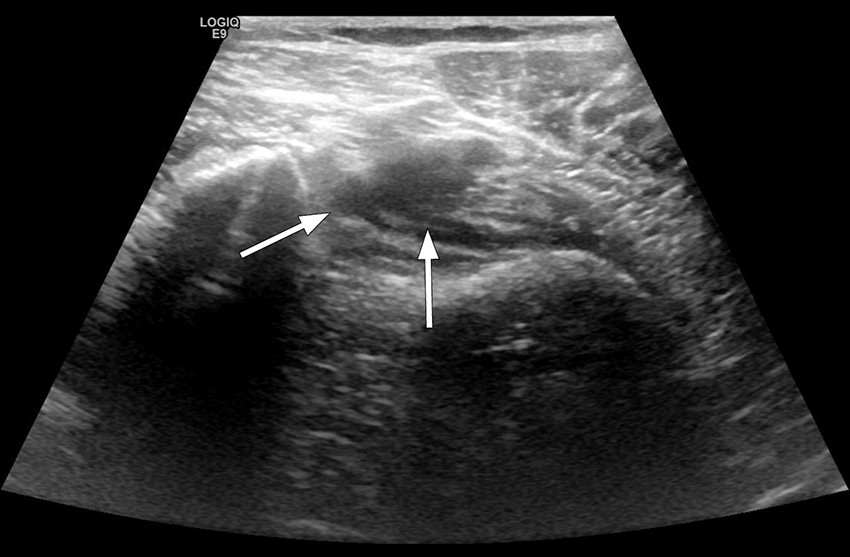

Dagen etter hadde hun fortsatt store smerter i knehasen og øvre del av leggen, og ba en kollega ved radiologisk avdeling om å gjøre en ultralydundersøkelse for å utelukke dyp venetrombose. Det ble da påvist en trombe i distale vena poplitea (figur 1).